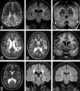

Leukodystrophies

Leukodystrophies are a group of usually inherited disorders characterized by degeneration of the white matter in the brain. The word leukodystrophy comes from the Greek roots leuko, "white", dys, "abnormal" and troph, "growth". [Source: Wikipedia ]